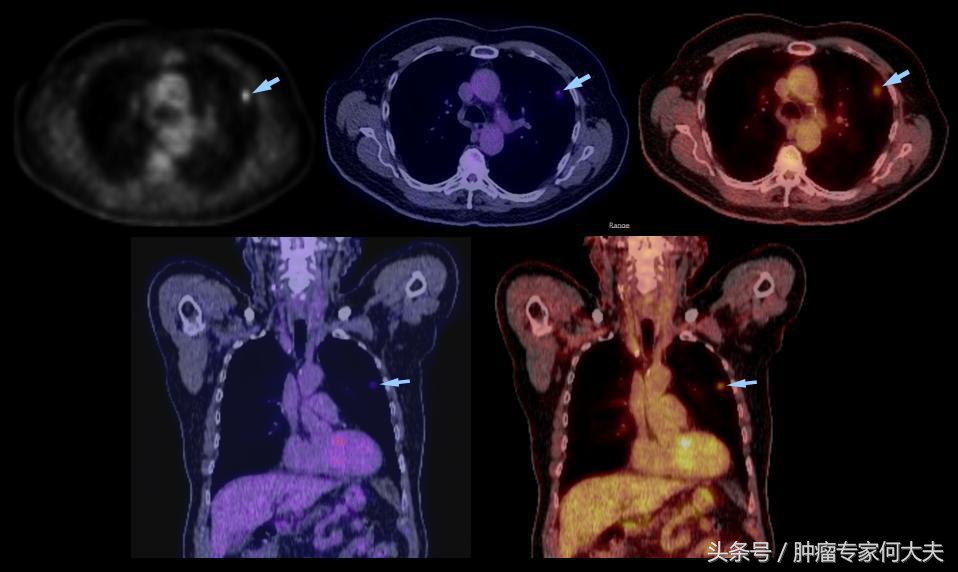

在第二年接近第三年的那次复查中,小豆被医生告知右肺也长了瘤子,医生建议小豆穿刺活检,小豆还是比较配合的,做了肺穿刺活检术,术后病理结果证实也是肺腺癌,和以前病理结果一样,医生推测可能是转移,并对取下的组织进行了基因检测,仍然没有检测到敏感突变基因,但医生建议小豆可以尝试口服“易瑞沙”,因为在生病的2年多时间里,小豆研读了很多肺癌的专业书籍,对肺癌的知识了解甚多,因此她同意了口服靶向药,在口服靶向药的两个月里,除过面部皮疹,没有其他不良反应,但用药三个月后,复查肺部CT,病灶依然没有明显变小迹象。医生考虑无效,于是就把靶向药停了。没有任何治疗,她还能撑多久?她自己不知道,医生们也众说纷纭,反正总体是时间不会太久,有的医生说也就半年一年左右,小豆说当时自己想“反正都这样了,与天争命也无济于事,静静等待未来会发生什么”。

肺相关淋巴

就这样,读书、看报、上网,有时候和朋友出去游游逛逛,虽然癌症在身,她不能积极作为,只能听天由命,但是半年过去了,右肺出现的病灶生长势头不明显,一年过去了,两年过去了,三年过去了,一直在复查,但是复查的结果总是说变化不显著。但医生仔细对比三年之初与三年之末(最近)的片子,瘤子是有所长大,但都长的不算多,个别小病灶甚至自然变小。 最近,小豆说自己喘的明显了,夜里咳嗽厉害,难以成眠,要来查查,我给做了胸部CT检查,结果提示两肺多发占位病变,对比了她3年前刚发现右肺时的片子,这次明显变大,目前尚未做出诊疗计划。但对于小豆这样的病人,实属少见。人类对于肿瘤的认识仍然处于很原始的阶段。就拿肺癌来说,现代医学研究算是比较成功的一种瘤种,已经认识到一部分肺癌患者因为存在某些基因突变可以从治疗中获益,但是没有突变的患者并不是一定就很危险,个体差异相当大。希望每个人不要因为得了肿瘤,就自暴自弃。